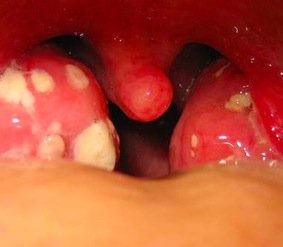

Malattia Del Bacio Che Cosa Fare Se Tuo Figlio Ha Preso La

Mononucleosi Infettiva Contagio Durata Conseguenze

Mononucleosi O Virus Dei Nuotatori I Sintomi E La Cura

Mononucleosi Sintomi E Cura Farmacia San Giuseppe

Mononucleosi Come Riconoscerla E Curarla

Mononucleosi Infettiva

Come Si Cura La Mononucleosi

Mononucleosi In Adulti E Bambini Biopills

Mononucleosi Infettiva Wikiwand